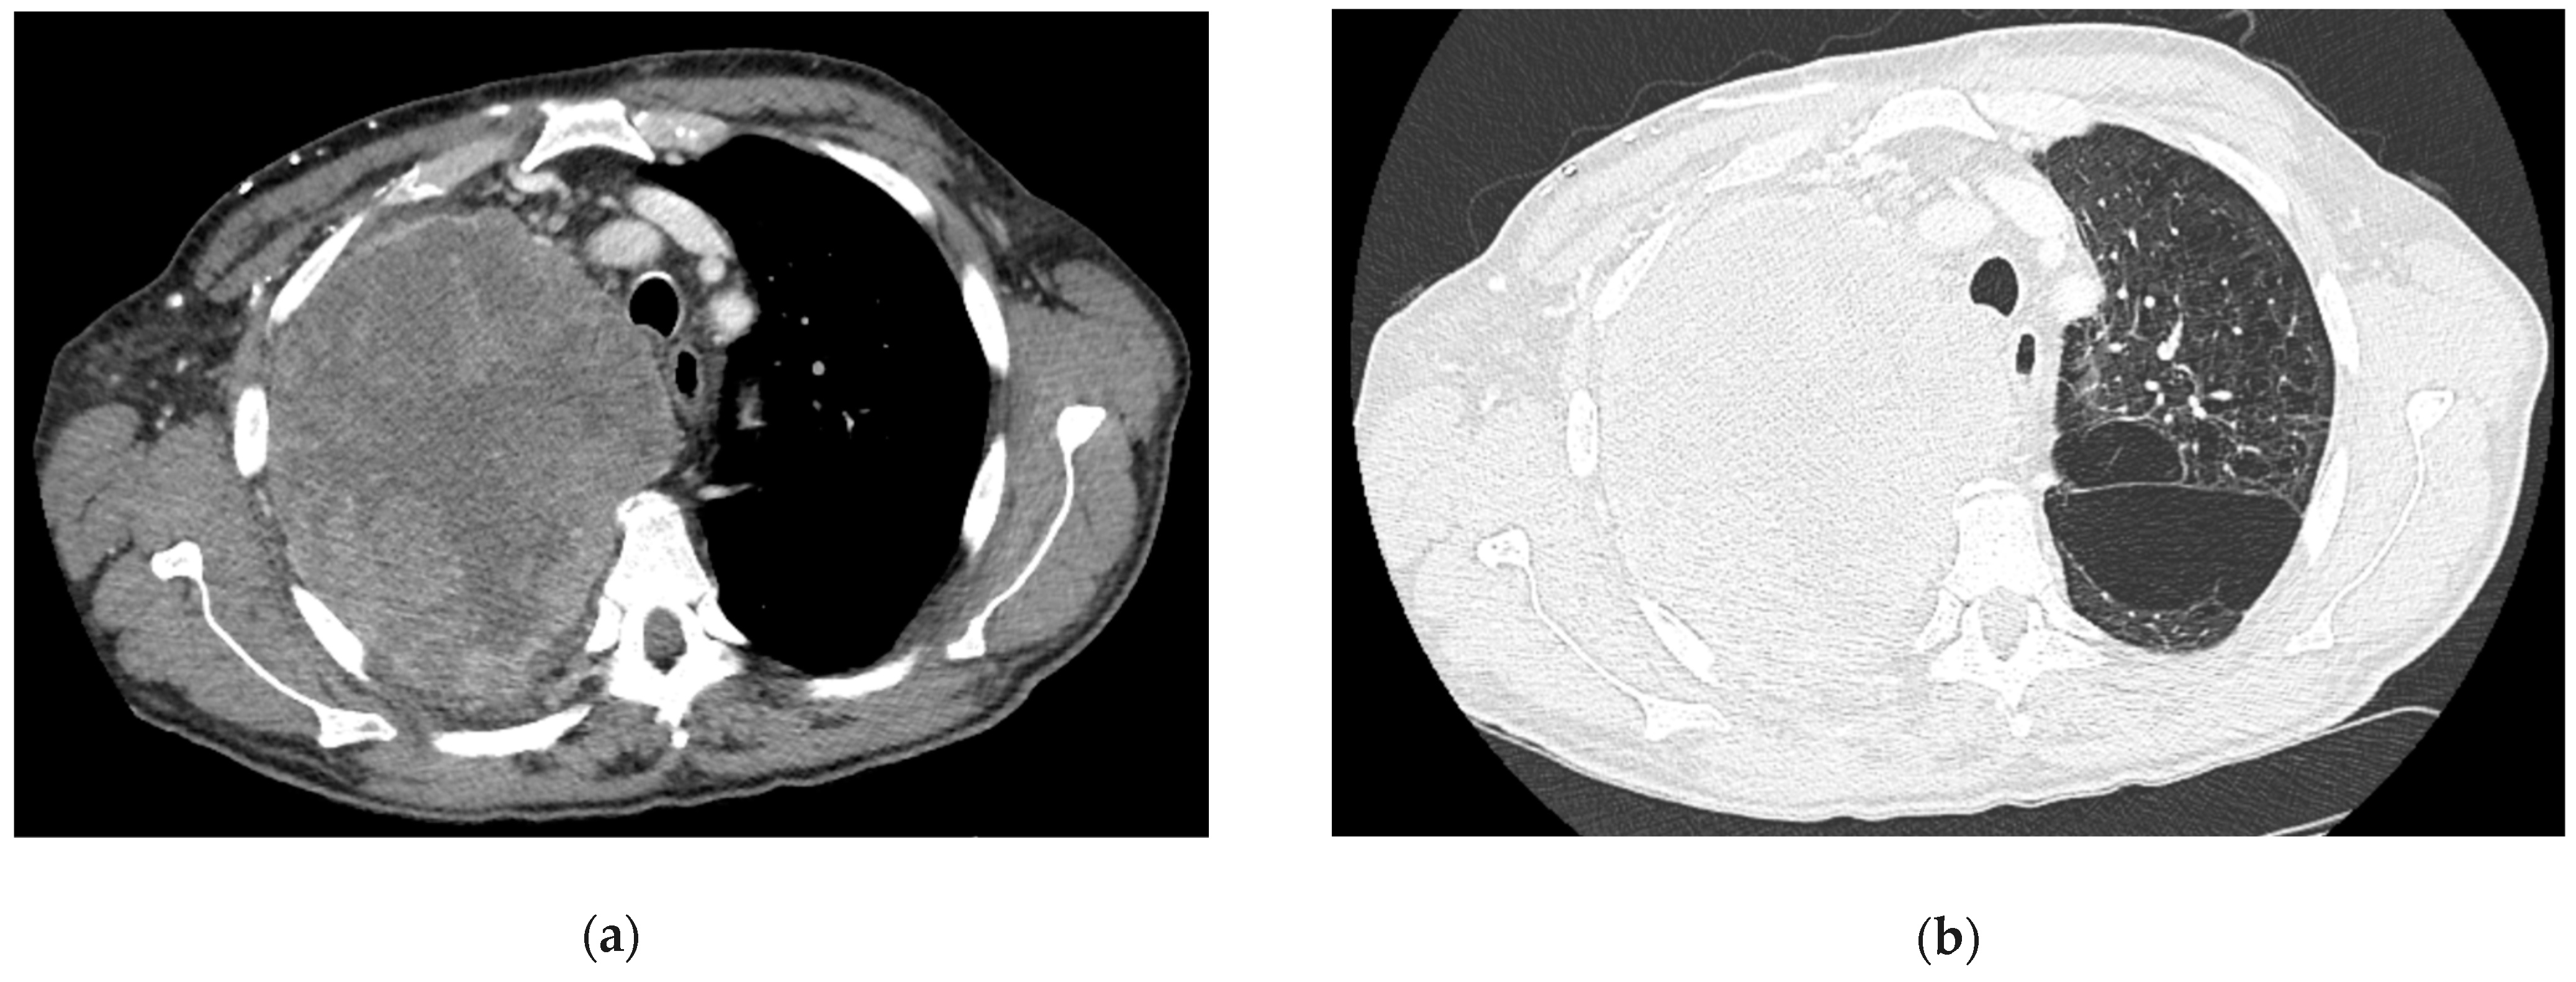

- Iguchi, T.; Hiraki, T.; Matsui, Y.; Fujiwara, H.; Sakurai, J.; Masaoka, Y.; Uka, M.; Tanaka, T.; Gobara, H.; Kanazawa, S. CT Fluoroscopy-Guided Core Needle Biopsy of Anterior Mediastinal Masses. Diagn. Interv. Imaging 2018, 99, 91–97. [Google Scholar] [CrossRef] [PubMed]

- Drumm, O.; Joyce, E.A.; de Blacam, C.; Gleeson, T.; Kavanagh, J.; McCarthy, E.; McDermott, R.; Beddy, P. CT-Guided Lung Biopsy: Effect of Biopsy-Side Down Position on Pneumothorax and Chest Tube Placement. Radiology 2019, 292, 190–196. [Google Scholar] [CrossRef]

- Navin, P.J.; Eickstaedt, N.L.; Atwell, T.D.; Young, J.R.; Eiken, P.W.; Welch, B.T.; Schmitz, J.J.; Schmit, G.D.; Johnson, M.P.; Moynagh, M.R. Safety and Efficacy of Percutaneous Image-Guided Mediastinal Mass Core-Needle Biopsy. Mayo Clin. Proc. Innov. Qual. Outcomes 2021, 5, 1100–1108. [Google Scholar] [CrossRef]

- Petranovic, M.; Gilman, M.D.; Muniappan, A.; Hasserjian, R.P.; Digumarthy, S.R.; Muse, V.V.; Sharma, A.; Shepard, J.-A.O.; Wu, C.C. Diagnostic Yield of CT-Guided Percutaneous Transthoracic Needle Biopsy for Diagnosis of Anterior Mediastinal Masses. AJR Am. J. Roentgenol. 2015, 205, 774–779. [Google Scholar] [CrossRef]

- Skretting, I.K.; Ruud, E.A.; Ashraf, H. Diagnostic Yield, Complications, Pathology and Anatomical Features in CT-Guided Percutaneous Needle Biopsy of Mediastinal Tumours. PLoS ONE 2022, 17, e0277200. [Google Scholar] [CrossRef]